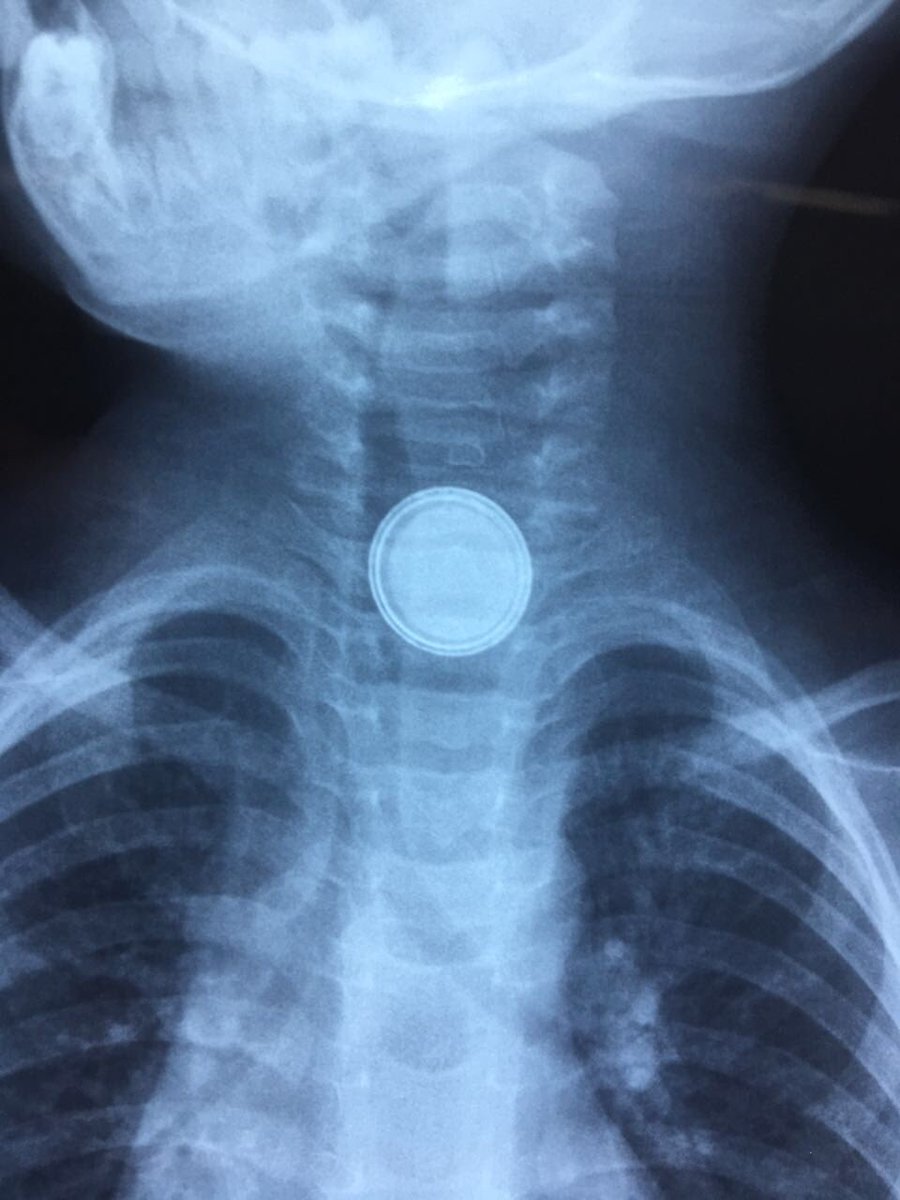

تمكن فريق طبي من مستشفى عرعر المركزي من إنقاذ حياة طفل يبلغ من العمر سنتين ابتلع “بطارية”.

وأوضح الحساب الرسمي لصحة الشمالية على موقع “تويتر” أن الفريق الطبي تمكن من استخراج القطعة الحديدية في زمن قياسي عبر عملية بواسطة المنظار تكللت بالنجاح.

ولفتت صحة الشمالية إلى أن حالة الطفل مستقرة الآن.